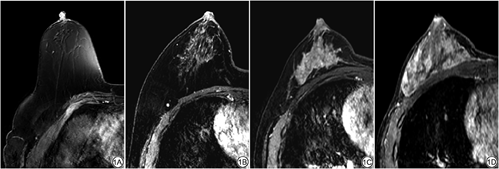

依据美国放射学院2013版BI-RADS,在DCE-MRI注射对比剂后第一期图像中选取健侧乳腺评价BPE,由两名分别从事乳腺影像诊断5年和16年的放射科医生独立阅片,采用目测四分法依据纤维腺体组织强化范围分为四类:极少(<25%腺体组织强化)、轻度(25%~50%腺体组织强化)、中度(51%~75%腺体组织强化)、重度(>75%腺体组织强化)[16] (图1),若二者判读存在分歧协商后达成一致。